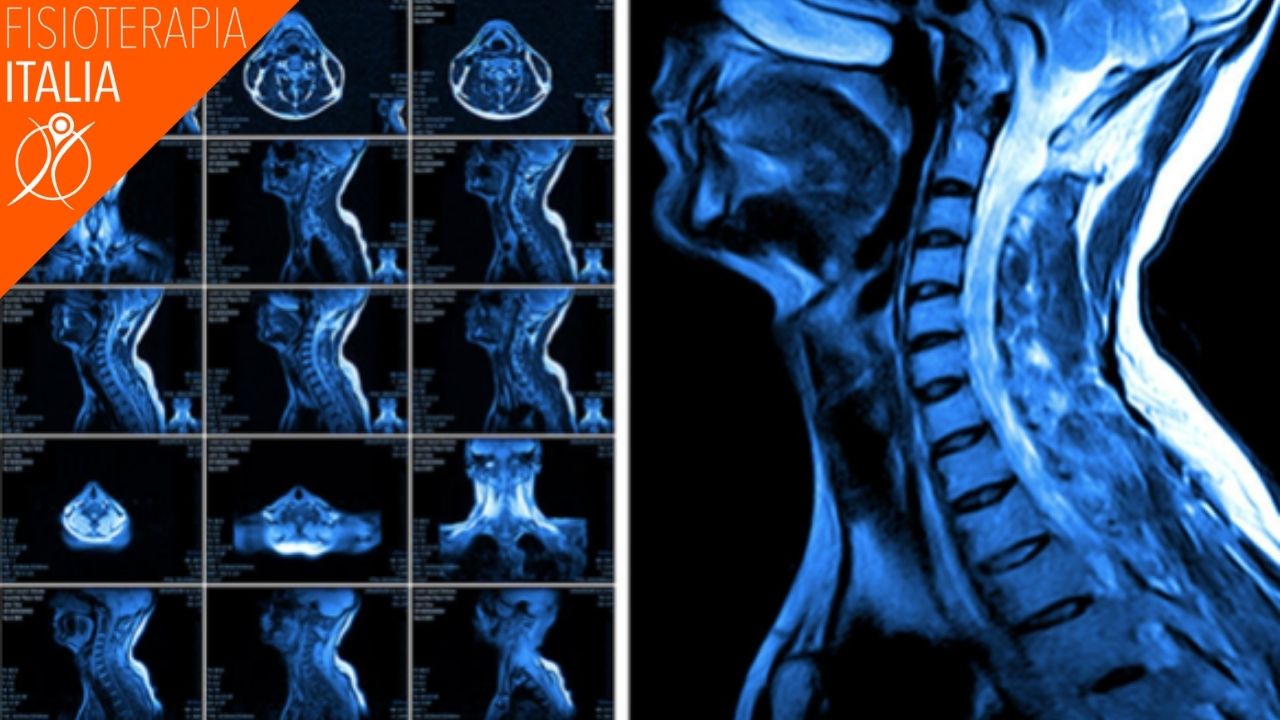

TEST DI IMAGING

Una lesione da colpo di frusta non è evidente nei test di imaging, ma il medico probabilmente ne prescriverà uno o più di uno per poter escludere altre condizioni patologiche.

I test di imaging includono: